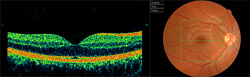

Aquesta tècnica avalua, mitjançant imatges, les capes de la retina, visualitzant-se un tall transversal de la zona de la retina desitjada. Davant la més mínima alteració entre les capes (com és el cas de la DMAE) i gràcies a les diferents prespectives visuals que ofereix el seu software, qualsevol alteració quedarà projectada, mesurada, comparada i monitoritzada. Així mateix permet també l'obtenció en 3D de la retina avaluada.

Compta amb una base de dades (estudis de població) que ens compara automàticament l'espesor de les fibres ganglionars de la retina que es dirigeixen al nervi òptic per valorar el seu rang de normalitat. És per això de gran utilitat en el cas de pacients amb glaucoma, tant com a suport en el diagnòstic com en el seguiment a futures revisions.